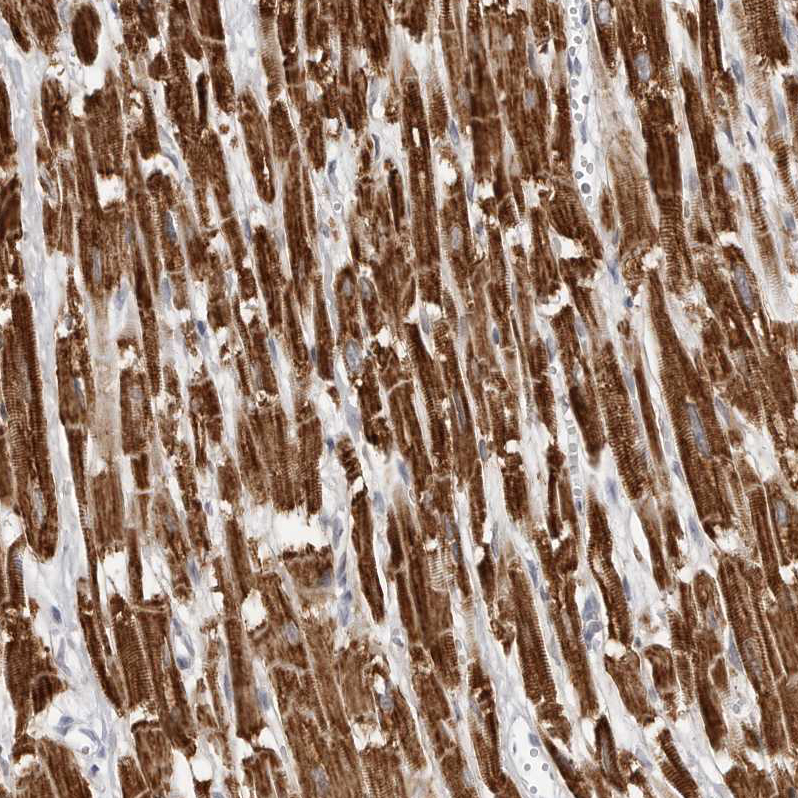

Immunohistochemical staining of human heart muscle shows strong granular cytoplasmic positivity in cardiomyocytes.